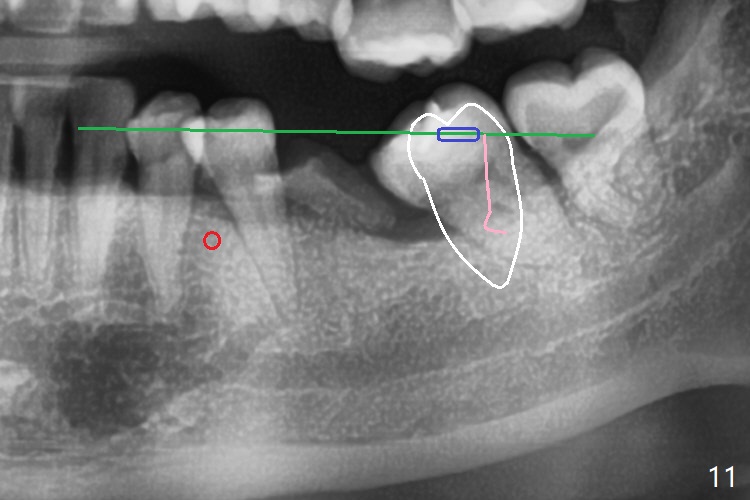

初步计划:第一期安置矫正器,排列,建立正常前牙覆合覆盖,二类牵拉。尽量竖直左下7,8(图十一:白色轮廓);使用两个微型植体(图九:黑线(两个植体之间放置power chain(红线)))压入左上6(图十(圆圈:近中微型植体),与图三对比),为左下7近中移位(红色箭头)创造空间。

第二期在左下4和5之间植入微型植体作为支抗(图十一:红色),利用7远中长勾(粉红色)和橡皮筋,先让7平行近中移位,控制根torque。A 31-year-old woman with Class II Division I malocclusion requests orthodontic treatment without extraction of LL8. U8s and LL6 have been extracted with SRP. The 1st stage will be alignment , intrusion of UL6, upright of LL7 and 8 and correction of Class II malocclusion using double twin.